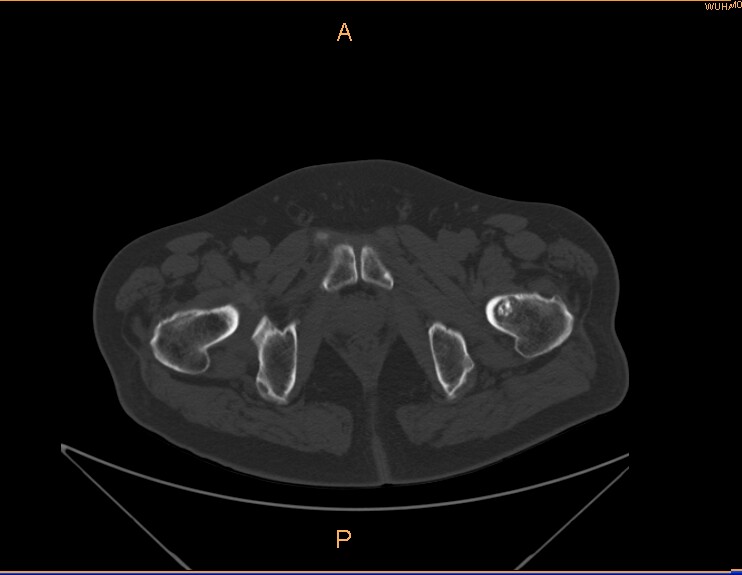

标题: CT29088:左股骨颈 [打印本页]

标题: CT29088:左股骨颈

左侧股骨颈疼痛。

左股骨颈软骨瘤可能,建议增强或mri

内生软骨瘤。

不排除骨样骨瘤

不排除左侧股骨颈内生软骨瘤可能。

内生软骨瘤年龄较小,分叶状,局部皮质有改变,钙化为环形半环形,没有这么粗大。

左股骨颈软骨瘤可能,建议增强或mri  。